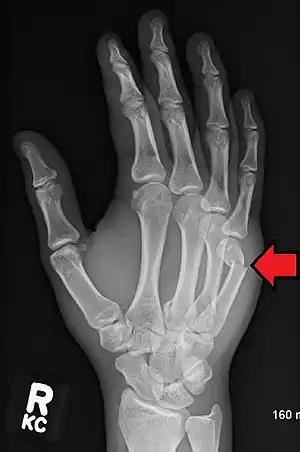

| Boxer's fracture | Boxers | fracture at the neck of the fifth metacarpal | punching solid object | Boxer's fracture Archived 2007-07-15 at the Wayback Machine at Wheeless' Textbook of Orthopaedics online |